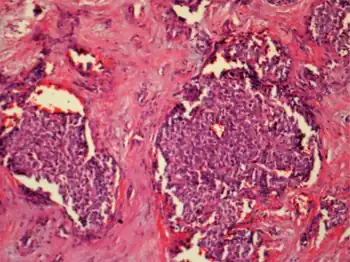

| Diagrammatic representation of β-cell function, genetic defects are included in red.[1] | |